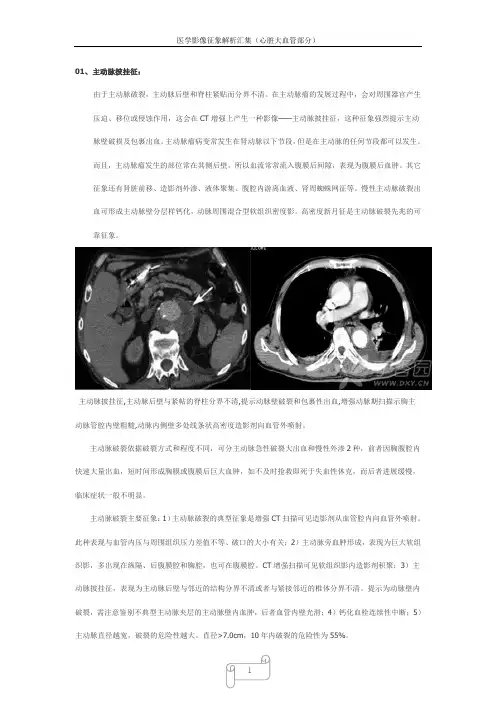

01、主动脉披挂征:由于主动脉破裂,主动脉后壁和脊柱紧贴而分界不清。

在主动脉瘤的发展过程中,会对周围器官产生压迫、移位或侵蚀作用,这会在CT增强上产生一种影像——主动脉披挂征,这种征象强烈提示主动脉壁破损及包裹出血。

主动脉披挂征,主动脉后壁与紧帖的脊柱分界不清,提示动脉壁破裂和包裹性出血,增强动脉期扫描示胸主动脉管腔内壁粗糙,动脉内侧壁多处线条状高密度造影剂向血管外喷射。